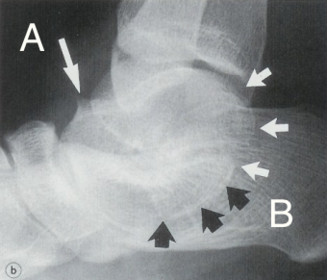

What is this? What is shown by A and B? | STJ coalition A = talar neck spurring B = Halo or 'C' sign |